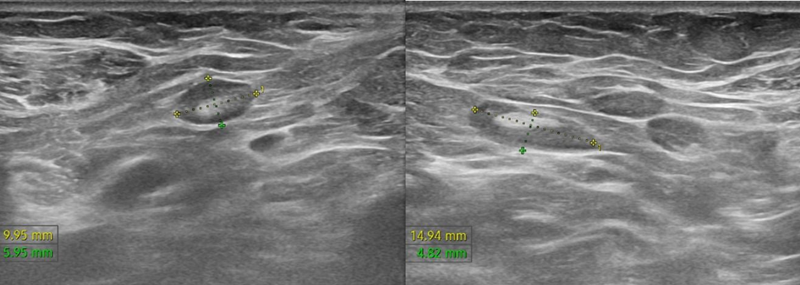

Trên siêu âm tuyến vú cho thấy hình ảnh nhân tuyến vú trái (BIRADS 5), kèm hạch hố nách hai bên.

Trên siêu âm cho thấy hình ảnh nhân tuyến vú trái (BIRADS 5), kèm hạch hố nách hai bên